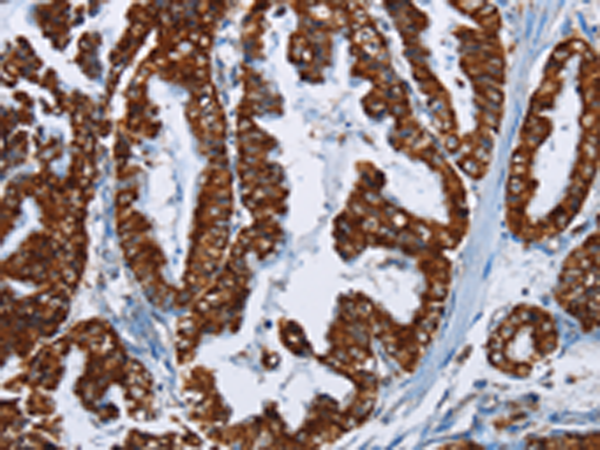

分类: 科研抗体货号: P04090别名: CT1.6; MAGE6; MAGE3B; MAGE-3b应用: IHC反应种属: Human